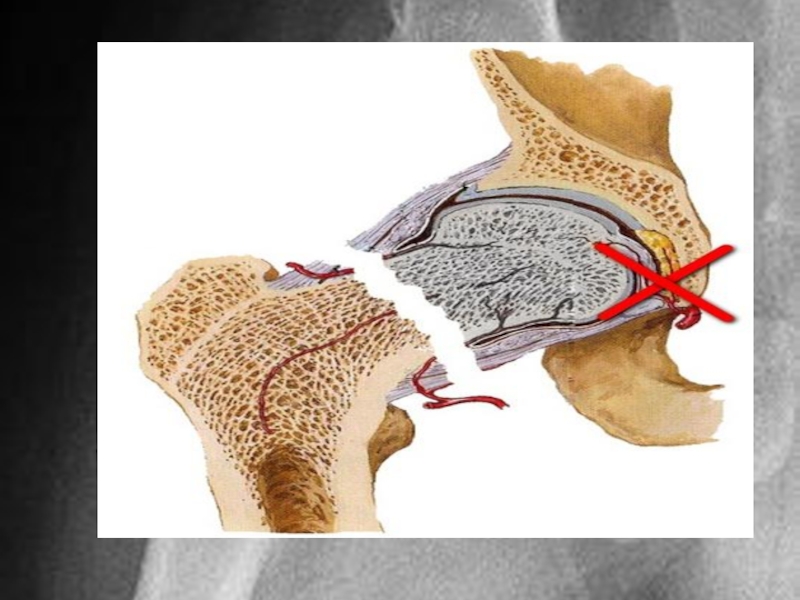

Слайд 156)Лечение:

Лечение медиальных переломов представляет большие трудности. Условия для сращения неблагоприятные в

связи с местными анатомическими особенностями и трудностью иммобилизации (обеспечения неподвижности). Костное сращение перелома наступает через 6-8 мес. В том же время длительный постельный режим у пожилых приводит к развитию застойной пневмонии, пролежней, тромбоэмболии, что и является основной причиной высокой летальности. Поэтому методы лечения, связанные с длительным обездвиживанием больного, в пожилом возрасте применяться не должны. Скелетное вытяжение и гипсовая тазобедренная повязка как самостоятельные методы лечения в настоящее время не используются.